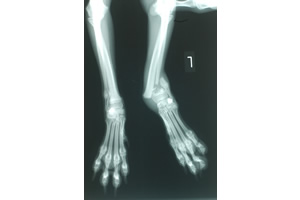

| ●52 今回の症例は、6カ月齢のパピヨンの左前肢橈尺骨の遠位成長板の骨折です。  |

市販のプレートではサイズが合わなかった為、X線写真を基に作製したT字プレートを装着しました。 骨折部遠位に横に3穴、そして近位の橈骨に5穴のホールをあけ2mmのスクリューで固定しました。  |

| 術後のX線写真ですが、ほぼ満足な固定が施されておりますが、発育途中の幼犬の成長板の骨折は多少なりとも必ず骨の発育に悪影響を及ぼしますので、術後の経過の観察が経日的に必要になります。 | ![]()  |